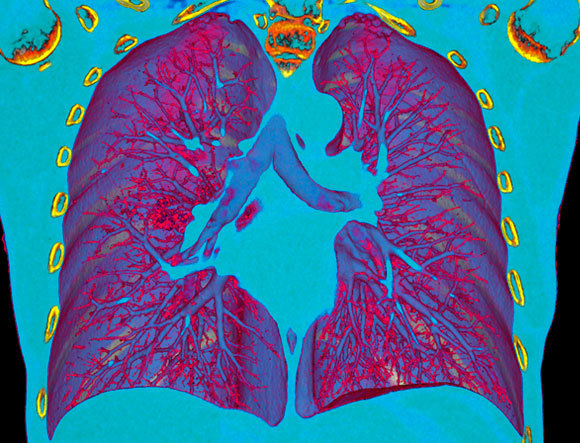

בדיקת CT מאפשרת לזהות את דלקת הריאות של חולה COVID-19 (הכתם האדום משמאל למרכז התמונה) | מקור: VSEVOLOD ZVIRYK / SCIENCE PHOTO LIBRARY